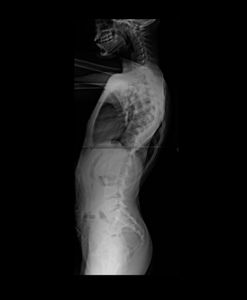

Há um ano, sua mãe reparou que ele começou a andar torto e comentou a situação comigo, Adriana, com quem ela trabalha ocasionalmente. Ofereci de levarmos o menino a um ortopedista particular e assim foi. Na consulta, o médico realizou exames de imagem (anexos a essa campanha) e, chocado, diagnosticou Juan com uma escoliose gravíssima, recomendando cirurgia em caráter de urgência.

De 1 ano para cá, desde o diagnóstico, a angulação da coluna de Juan tem piorado, apesar do uso do colete e do tratamento em sessões de RPG, e a cirurgia é inavitável.

Além da preocupação natural da família com o quadro geral, o grande receio é de que a coluna venha a comprometer o seu pulmão, já que Juan tem asma desde muito novo. Por isso, em razão da urgência e evolução gradativa do quadro, lançamos essa campanha! O valor arrecado será integralmente destinado à cirurgia e ao tratamento da escoliose de Juan.